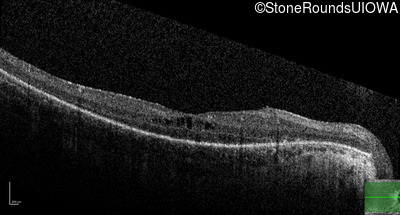

Optical Coherence Tomography - Right - 20/40

Exemplar / OCT Stack